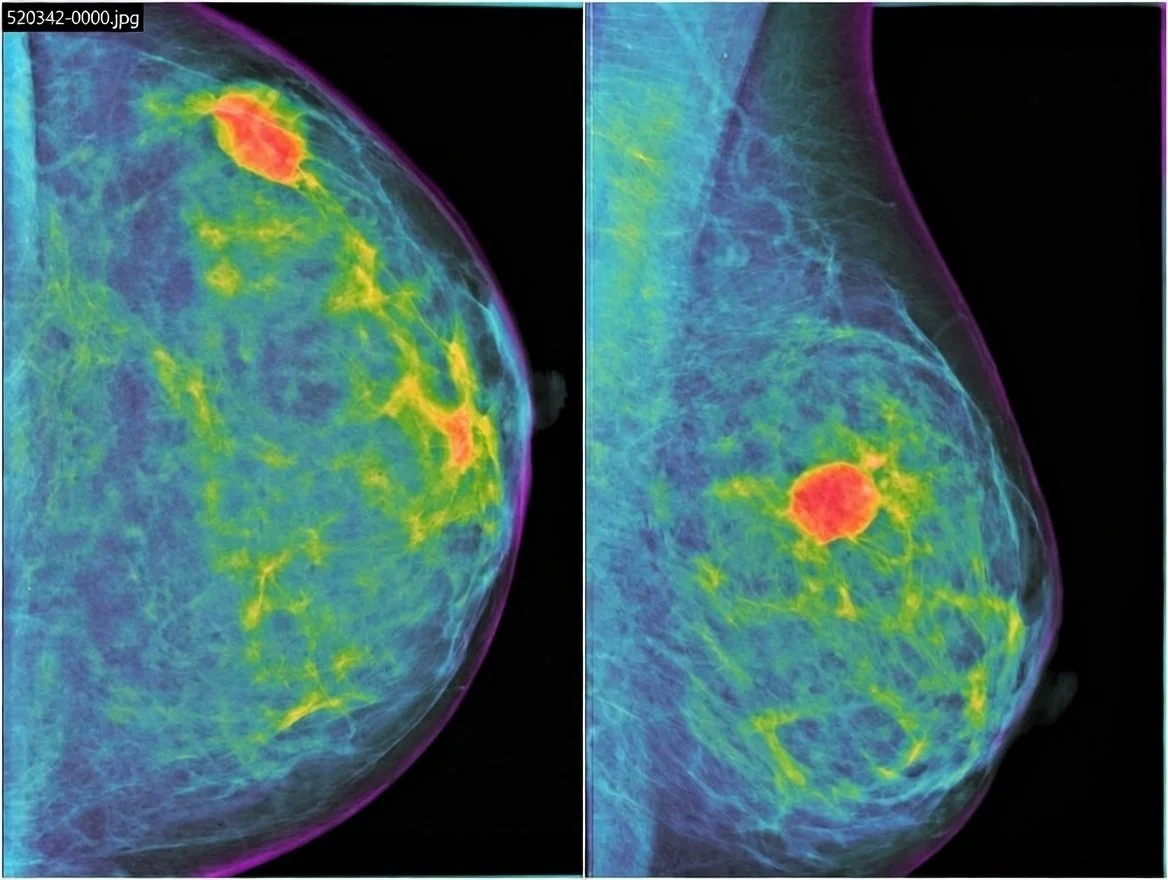

El cáncer de mama triple negativo, uno de los subtipos más agresivos y difíciles de detectar —a veces invisible en mamografías y ecografías—, podría tratarse en el futuro con vacunas personalizadas capaces de entrenar al sistema inmunitario para prevenir recaídas. Cortesía: Precision Imaging Centers

Imagen mamográfica coloreada de un cáncer de mama triple negativo: una masa de contorno ovalado y bordes bien definidos en gran parte de la lesión, pero con zonas difusas que dificultan su identificación, un rasgo que complica el diagnóstico de este tumor agresivo para el que se investiga una vacuna personalizada.